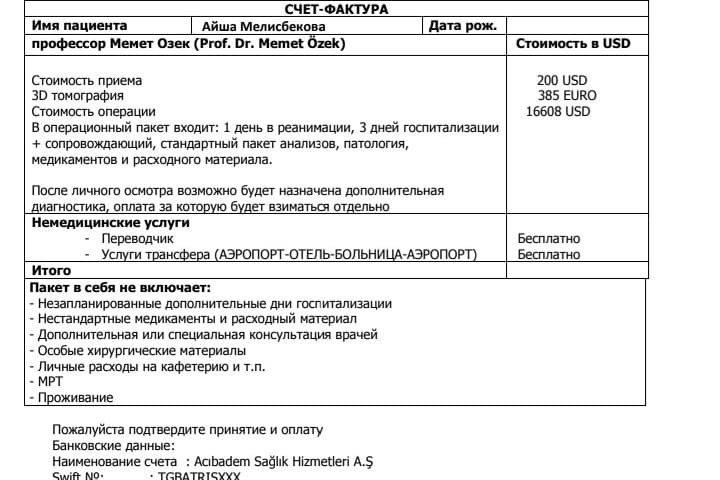

A️isha Melisbekoba was born with Spina Bifida myelomeningocele, syndrome of fixed spinal cord at 29 weeks. Doctors say that people born with this diagnosis will not live long. But with proper treatment on time she will survive. So far she had 2 operations on her spinal cord. Her spine is torn, spinal cord is protruding, and there is water in 1/3 of her head.

Aisha needs an operation on her spinal cord in Turkey, so she will be able to move her legs. It will be her 3rd operation.

Diagnosis: CMD of the central nervous system Spina bifida myelomeningocele, fixed spinal cord syndrome. Kyphotic spinal deformity. Internal hydrocephalus, Arnold-Chiari type 2 anomaly. Peripheral paralysis of both legs. CHD, DMPP. CHF of the MPS hydronephrotic transformation of the left kidney, incomplete doubling of the left kidney. Urine and callus retention. Condition after: ventriculo-peritoneal shunting from 04/16/2019. And excision of the spinal hernia from 10/29/2019.

АИШАНЫН ОПЕРАЦИЯСЫ үчүн сиздерден жардам кылууңуздарды суранабыз. Аишага (21.02.2019 – жылы туулган) буга чейин эки жолу операция кылынды. Учурда ТУРЦИЯНЫН Стамбул шаарындагы ACIBADEM клиникасында операция кылууга 16608 USD + (кабыл алуу 200 USD+3D томография 385 EURO) жалпы 1496098 сом керек болууда. Азыркы учурда кайрымдуу адамдардын колдоосу менен 260000сом чогултулду. Аиша 29 жумалык боюмда бар кезде ушундай диагноз менен төрөлөрүн билгенбиз. Азыр Кудайга шүгүр 1 жаш 2 ай болуп калды. Дарыгерлер мындай диагноз менен төрөлгөндөр көпкө жашабайт дешет. Бирок убагында туура даарыласа жашап кетет экен. Кызымдын омурткалары ажырап, жүлүнү сыртка чыгып калган, башынын 1/3 бөлүгүндө суу бар. Буюрса, Түркиядан жүлүнгө операция жасатсак буттарынын кыймылдашына шарт түзүлөт. Кийинчерээк омурткасына операция жасалат».

A️isha Melisbekoba was born with Spina Bifida myelomeningocele, syndrome of fixed spinal cord at 29 weeks. Doctors say that people born with this diagnosis will not live long. But with proper treatment on time she will survive. So far she had 2 operations on her spinal cord. Her spine is torn, spinal cord is protruding, and there is water in 1/3 of her head.

Aisha needs an operation on her spinal cord in Turkey, so she will be able to move her legs. It will be her 3rd operation.

Diagnosis: CMD of the central nervous system Spina bifida myelomeningocele, fixed spinal cord syndrome. Kyphotic spinal deformity. Internal hydrocephalus, Arnold-Chiari type 2 anomaly. Peripheral paralysis of both legs. CHD, DMPP. CHF of the MPS hydronephrotic transformation of the left kidney, incomplete doubling of the left kidney. Urine and callus retention. Condition after: ventriculo-peritoneal shunting from 04/16/2019. And excision of the spinal hernia from 10/29/2019.

АИШАНЫН ОПЕРАЦИЯСЫ үчүн сиздерден жардам кылууңуздарды суранабыз. Аишага (21.02.2019 – жылы туулган) буга чейин эки жолу операция кылынды. Учурда ТУРЦИЯНЫН Стамбул шаарындагы ACIBADEM клиникасында операция кылууга 16608 USD + (кабыл алуу 200 USD+3D томография 385 EURO) жалпы 1496098 сом керек болууда. Азыркы учурда кайрымдуу адамдардын колдоосу менен 260000сом чогултулду. Аиша 29 жумалык боюмда бар кезде ушундай диагноз менен төрөлөрүн билгенбиз. Азыр Кудайга шүгүр 1 жаш 2 ай болуп калды. Дарыгерлер мындай диагноз менен төрөлгөндөр көпкө жашабайт дешет. Бирок убагында туура даарыласа жашап кетет экен. Кызымдын омурткалары ажырап, жүлүнү сыртка чыгып калган, башынын 1/3 бөлүгүндө суу бар. Буюрса, Түркиядан жүлүнгө операция жасатсак буттарынын кыймылдашына шарт түзүлөт. Кийинчерээк омурткасына операция жасалат».